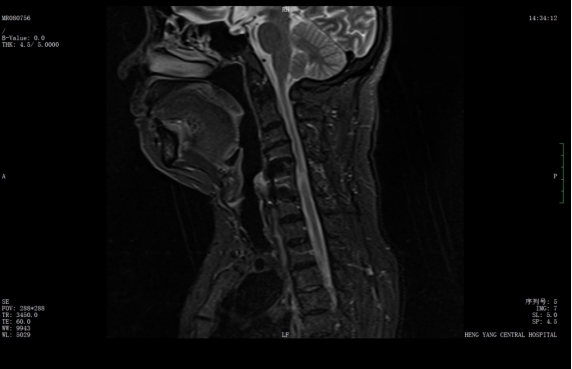

經(jīng)過精準(zhǔn)手術(shù)和術(shù)后系統(tǒng)的康復(fù)治療,患者神經(jīng)功能得到明顯恢復(fù),四肢肌力及感覺逐步改善,術(shù)后肌力達到IV級左右。復(fù)查X線顯示內(nèi)固定位置理想,患者非常滿意。出院之際,患者及家屬對衡陽市中心醫(yī)院的醫(yī)療技術(shù)、護理服務(wù)及醫(yī)聯(lián)體轉(zhuǎn)診效率均給予高度評價。

術(shù)后x線內(nèi)固定位置理想